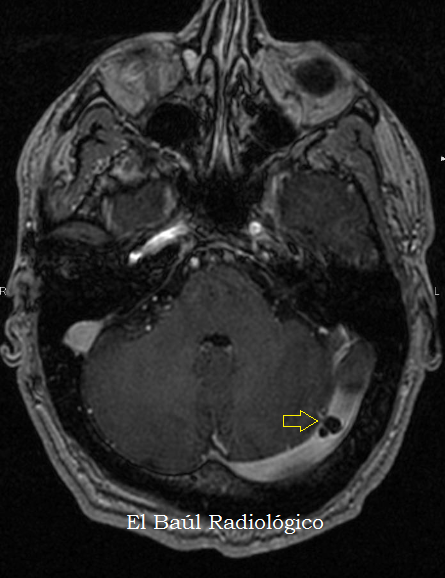

Las granulaciones aracnoideas (también vellosidades aracnoideas y granulaciones o cuerpos pacíferos) son pequeñas protuberancias de la materia aracnoidea (la segunda capa delgada que cubre el cerebro) en la membrana externa de la duramadre (la capa externa gruesa). Sobresalen en los senos venosos durales del cerebro y permiten que el líquido cefalorraquídeo (LCR) salga del espacio subaracnoideo y entre en el torrente sanguíneo.

Las mayores granulaciones se encuentran a lo largo del seno sagital superior, un gran espacio venoso que va de delante a atrás a lo largo del centro de la cabeza (en el interior del cráneo). Sin embargo, también están presentes en otros senos durales.

En la superficie interna de los huesos craneales se producen pequeñas fosas llamadas fóvea granular por granulaciones aracnoideas.[2][3]